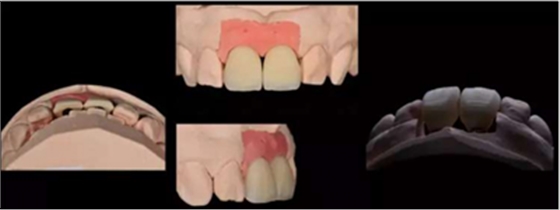

技師獲得模型后,行DSD設(shè)計(jì),根據(jù)患者口內(nèi)情況、咬合關(guān)系及患者意愿進(jìn)行牙齒形態(tài)調(diào)整。根據(jù)DSD設(shè)計(jì)進(jìn)行診斷蠟型制作。制作過(guò)程中需充分考慮影響美學(xué)重建修復(fù)的因素,包括中切牙寬長(zhǎng)比、牙齒形態(tài)、牙齦曲線、切緣弧度(咬合關(guān)系)等。

制作診斷蠟型:

可以觀察到鄰牙形態(tài)為尖圓形,為了獲得一個(gè)美觀效果且能關(guān)閉黑三角,牙齒形態(tài)由鄰牙的尖圓形改為方圓形。

蠟型制作完成后,翻制硅橡膠導(dǎo)板,根據(jù)穿齦輪廓來(lái)修整人工牙齦,保證修整后鄰緣的位置與診斷蠟型一致。即根據(jù)硅橡膠導(dǎo)板及齦緣修整牙齦范圍,隨后進(jìn)行穿齦輪廓的修整。

11,21 ASC 全瓷基臺(tái)一體冠蠟型

Asc基臺(tái)數(shù)字化設(shè)計(jì)

螺絲通道改變25°

通過(guò)改變螺絲通道角度,調(diào)整螺絲開(kāi)口位置